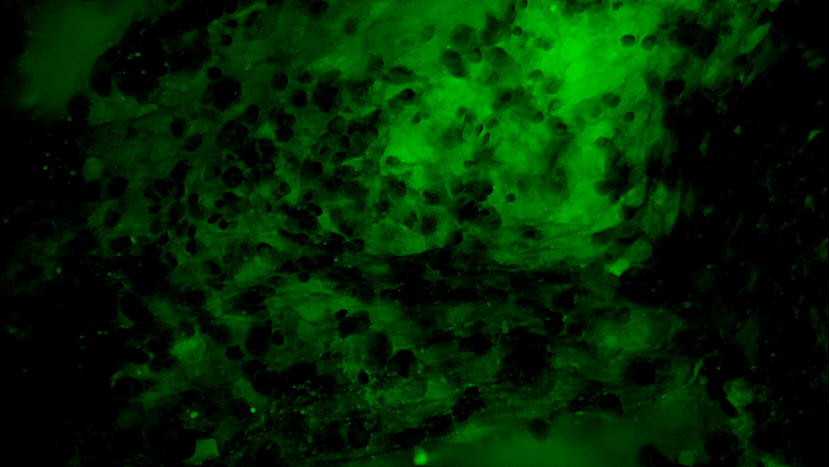

术中EndoSCell®细胞图像如下:

可疑组织的肿瘤细胞残留:细胞核异型性显著,分布密集且不规则